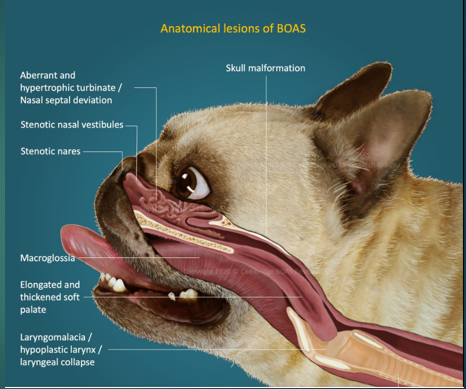

Brachycephalic obstructive airway syndrome in Dogs

Bulldog

Pug

Pekingese

French Bulldog

Boxer

Stenotic nares

Narrowing of the nasal passages, this increases resistance, making breathing in and out more difficult for the paitent

Oversized tongue

Tongue is too big for their moth, can push on soft plate

Elongated soft palate

Effects the epiglottis so can aspirate more easily

Hyperplastic larynx

Overgrowth of soft tissue in the larynx, leading to obstruction

Hypoplastic trachea

Trachea is narrower

Brachycephalic obstructive airway syndrome

The problems we see in these breeds are the consequences of trying to move air with all this increased resistance. To breathe they need to move O2 through the resp tract to the lungs, these issues with the soft tissues that we’ve highlighted cause resistance to air flow, this then increases Resp effort and rate to get more air in, this increases the negative pressure which makes the issue worse – negative pressure caused by them trying to overcome the resistance means that we get more resistance, more swelling of soft tissues and thus more negative pressure. We will often see abdominal effort with BOAS breathing.